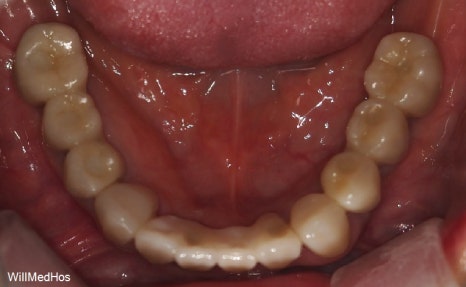

최종 치료 완료된 구강 모습입니다. 앞전의 구강 사진과 비교해보시면 자연스러운 치아의 모습이 완성된것을 확인 할수 있습니다.